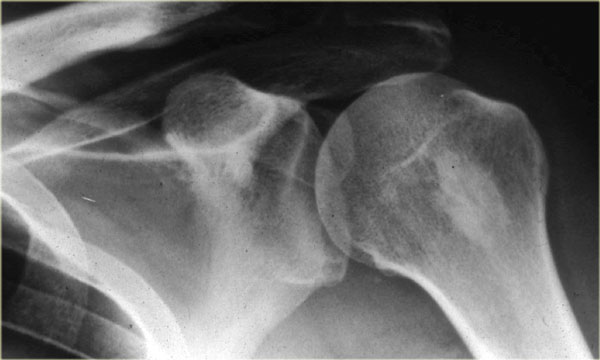

On the left a typical broad-based osteochondroma arising from the proximal humerus.

The major part of the bony protrusion consists of fatty bone marrow.

There is a thin peripheral cartilage cap, i.e. no suspicion for malignant degeneration.